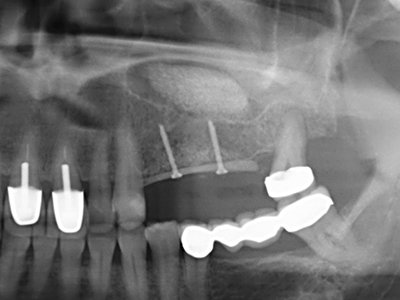

Bei der Knochenblockentnahme zeigen sich weitere Vorteile für die Piezochirurgie: Neben der bereits beschriebenen hohen Präzision bei der Osteotomie stellt sich gerade die Verwendung der dünnen Sägespitzen als besonders materialschonend heraus. Bei der Verwendung insbesondere von Lindemannfräsen sind mit deutlich höheren Entnahmeverlusten durch die dickere Instrumentenspitze zu rechnen (Lakshmiganthan, Gokulanathan et al. 2012). Die insbesondere bei retromolar entnommenen Blocktransplantaten notwendige basale Abtrennung wird durch speziell hierfür vorgesehene rechtwinklige Sägen erleichtert, so dass die Piezochirurgie als präzises, übersichtliches und sicheres Verfahren zur retromolaren Knochenblockgewinnung angesehen wird (Happe 2007) (Abb. 1-12).